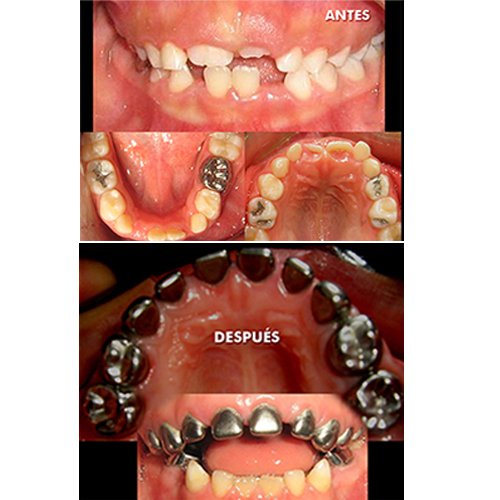

Conozca más casos dentales en nuestra Fanpage: ABC Clinica Dental dentista en guatemala. Implantes dentales